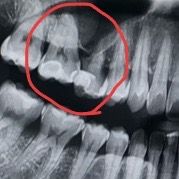

치료후 6일후 찍은 엑스레이 사진인데 혹시 뿌리 쪽에 염증이나 다른 문제가 있나 궁금합니다.

-> 사진에는 크게 문제는 없어보입니다.